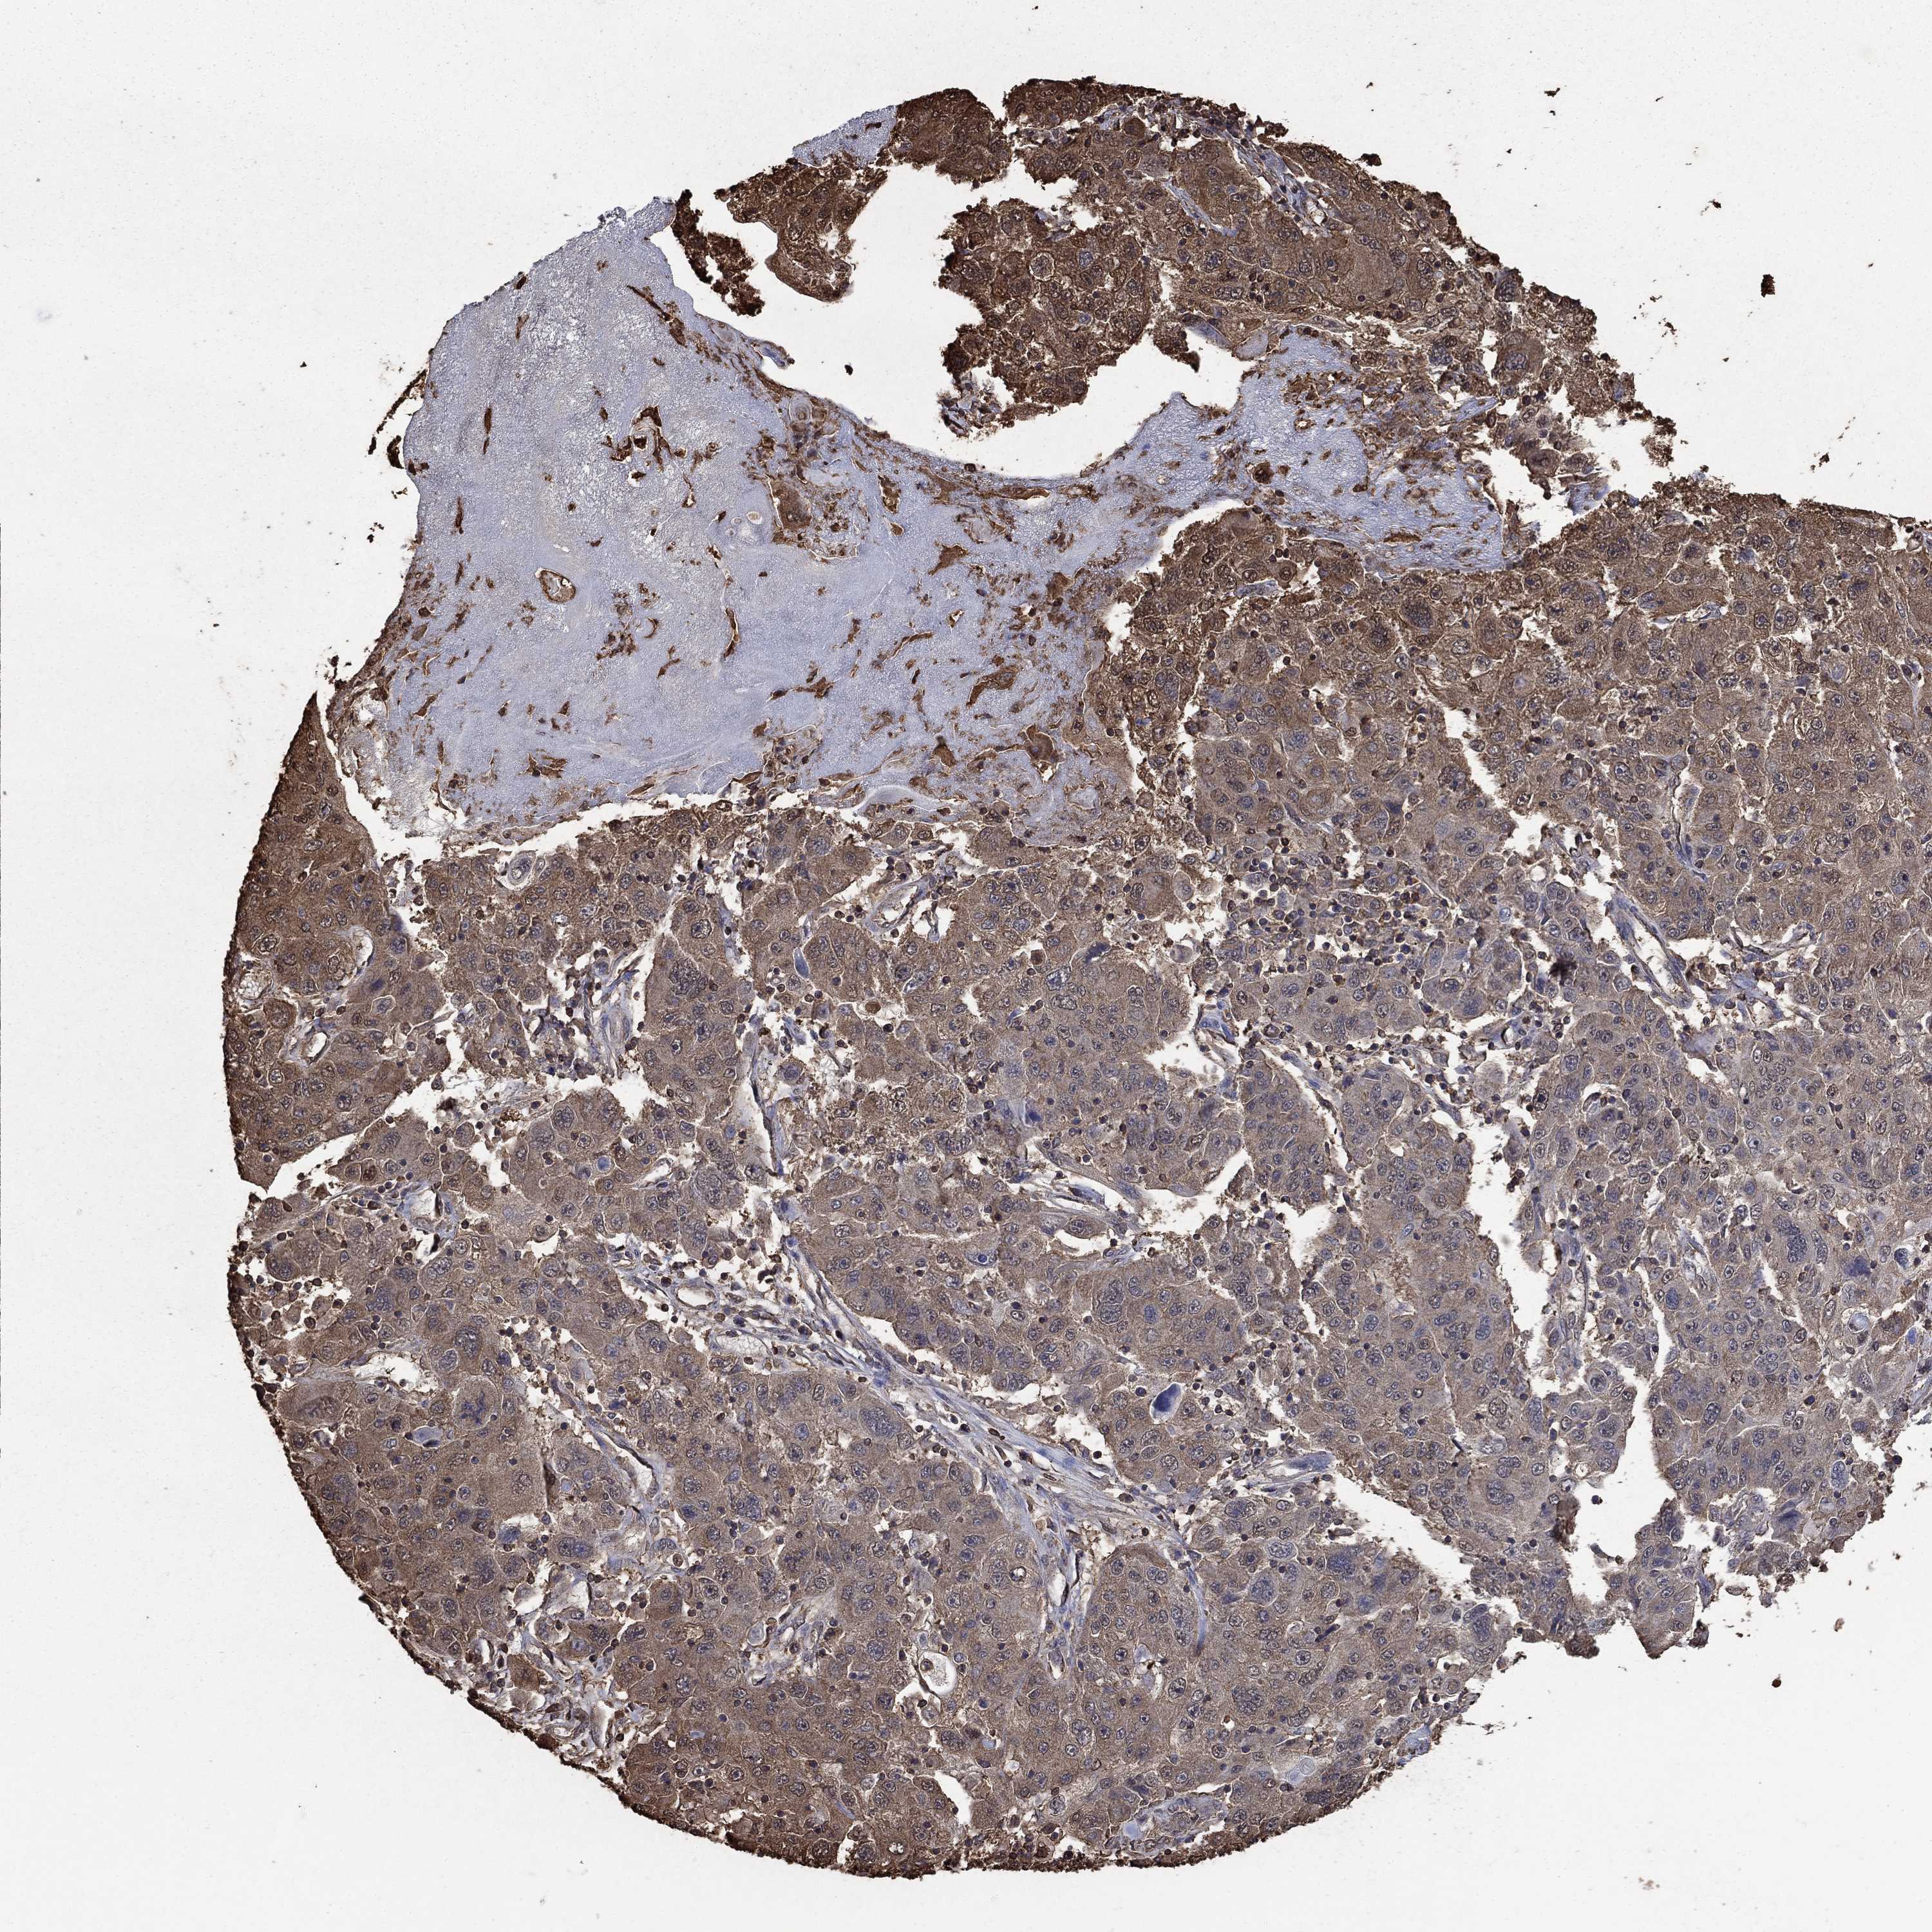

STOMACH CANCER - Protein expressioni

A mouse-over function shows sample information and annotation data. Click on an image to view it in a full screen mode. Samples can be filtered based on level of antibody staining by selecting one or several of the following categories: high, medium, low and not detected. The assay and annotation is described here.

Note that samples used for immunohistochemistry by the Human Protein Atlas do not correspond to samples in the TCGA dataset.

Antibody stainingi

Antibody staining in the annotated cell types in the current human tissue is reported as not detected, low, medium, or high, based on conventional immunohistochemistry profiling in selected tissues. This score is based on the combination of the staining intensity and fraction of stained cells.

Each image is clickable and will lead to virtual microscopy that enables deeper exploration of all samples and also displays staining intensity scores, fraction scores and subcellular localization as well as patient and tissue information for each sample.

HPA040067

HPA061280

CAB005197

CAB016392

CAB079968

Adenocarcinoma, NOS

Adenocarcinoma, High grade